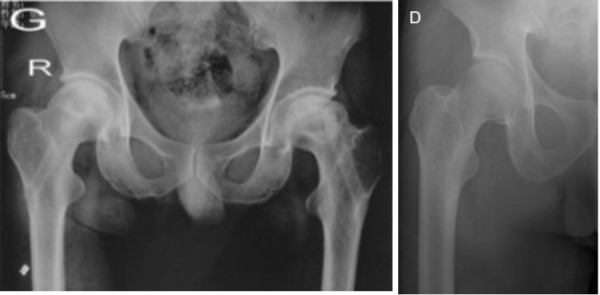

2.生物活性材料結(jié)合植骨,增強(qiáng)骨融合

3.提供足夠的力學(xué)支撐,防止股骨頭塌陷